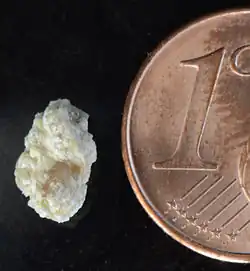

Nierensteine oder Nephrolithen (griechisch νεφρός nephrós, deutsch ‚Niere‘, und λίθος líthos ‚Stein‘) sind kristalline Ablagerungen (Harnsteine) des Nierenbeckenkelchsystems. Mit dem Eintritt in den Harnleiter werden sie zu Harnleitersteinen und können eine Kolik auslösen. Umgangssprachlich werden die Begriffe Nierenstein und Harnleiterstein – obwohl falsch – oft synonym gebraucht. Weitere Namen sind Nierenkonkrement, calculus renum[1] oder Calculus renalis. Eine Ansammlung vieler kleiner Nierensteine wird auch Nierengrieß genannt. Der medizinische Fachausdruck für die Nierensteinkrankheit ist Nephrolithiasis.

Als Extreme hinsichtlich Anzahl und Größe von Nierensteinen finden sich in der alten Fachliteratur Angaben von bis zu 1000 Konkrementen im rechten Nierenbecken und vom Gewicht eines einzelnen Nierensteins von 1088 Gramm (36 1/4 Unzen).[2]